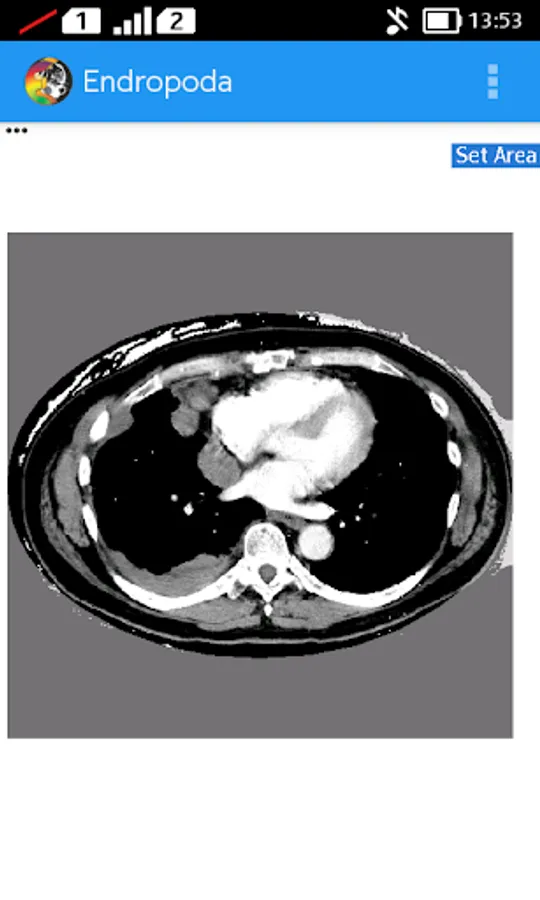

- HU mode : In this mode we can set the window width and window level of CT-Scan image to produce higher contrast higher contrast for certain organ, so it will be displayed better than another organ its surrounding. The basic principal of window technique is based on CT number. Where is CT number is a value related to attenuation coefficient of certain organ that can be used to distinguish an organ from another based on their attenuation coefficient.